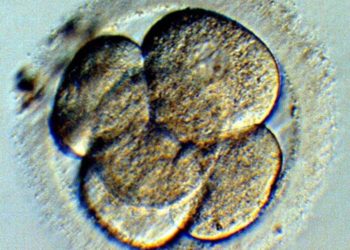

Antonio Lazcano Araujo, biólogo de la Universidad Nacional Autónoma de México, señaló que un embrión es un conjunto de células...